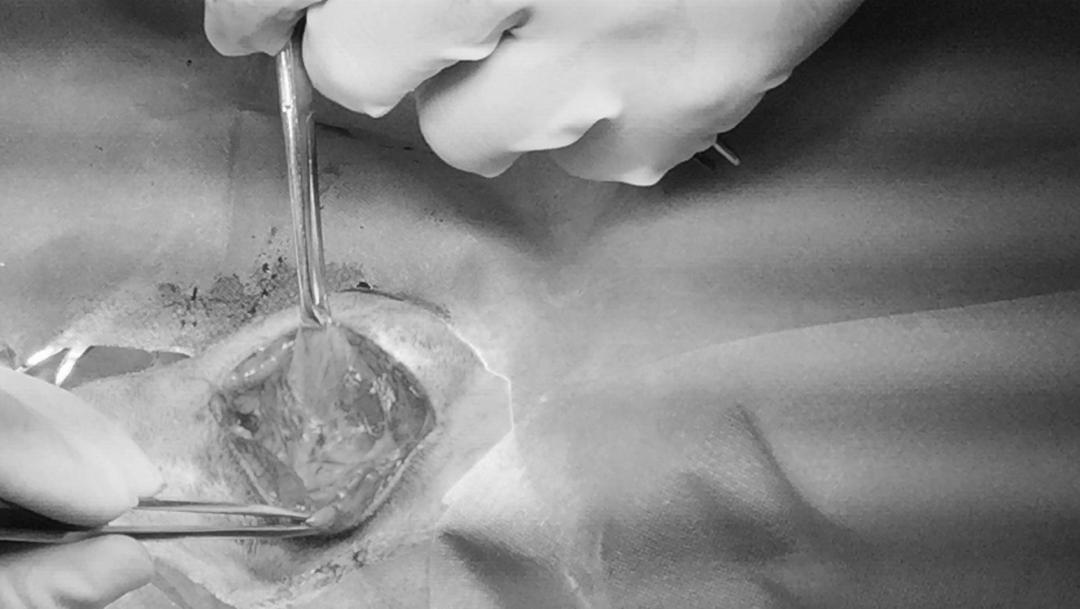

星星三月份因为车祸来医院就诊,痊愈后近期发现下颌长了一个大包,吃喝都正常感觉没有啥影响,在家一周未见好转带过来就医。

宠物刚到医院的照片

T38.5、精神状态良好,触诊肿物坚实,未见明显疼痛,B超检查可见两个液体腔,穿刺抽出黄色粘稠液体,细胞学未见细菌,肿瘤细胞。

唾液腺粘液囊肿

手术是公认的一线治疗方法,重复引流或注射抗菌消炎药物不能消除黏液囊肿,反而会导致脓肿和纤维化,导致手术更复杂。